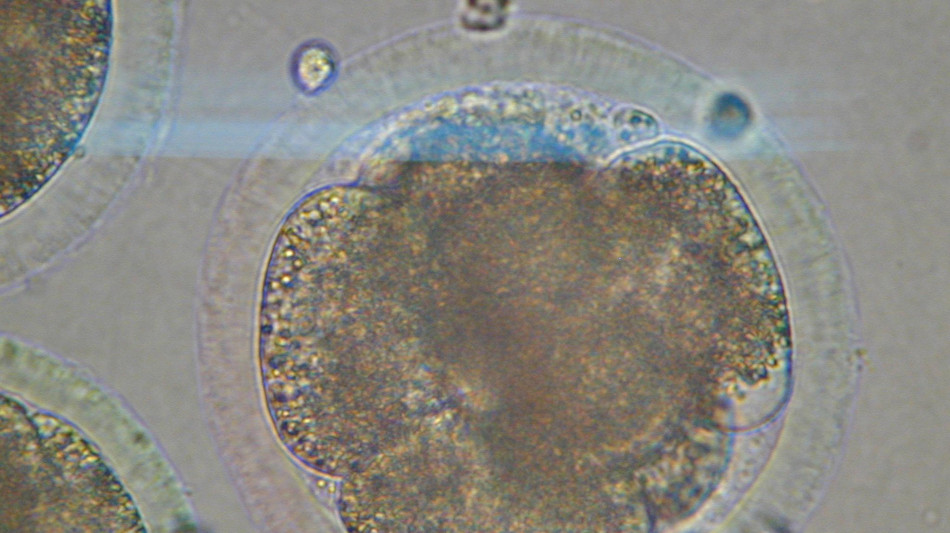

L'invecchiamento rimodella le cellule dei mammiferi

La scoperta nei topi. I segnali possibile bersaglio per future terapie

Il primo zoom sul processo di invecchiamento delle cellule indica che queste vengono rimodellate e che i cambiamenti avvengono in modo sincronizzato in ogni organo, aumentando il rischio di malattie tipiche dell'età avanzata come quelle cardiovascolari, i tumori e le demenze. E' un processo comune a tutti i mammiferi e, ora che sono stati scoperti, i segnali che lo contraddistinguono potranno diventare bersagli per future terapie. Lo indica la ricerca pubblicata sulla rivista Science e coordinata dalla Rockefeller University di New York, con il gruppo di Junyue Cao. La mappa è la prima ottenuta analizzando 7 milioni di cellule di 21 tessuti prelevati da topi giovani (un mese), di mezza età (cinque mesi) e anziani (21 mesi). Utilizzando una tecnica chiamata 'single-cell Atac-seq', in ciascuna cellula i ricercatori hanno analizzato lo stato di salute della struttura (chiamata cromatina) che impacchetta il materiale genetico per adattarlo al nucleo. E' emerso così che quando l'organismo invecchia, la composizione delle cellule e la disponibilità della cromatina cambiano in tutti i tipi di cellule e in modo particolare in quelle del sistema immunitario. Mentre queste si espandono, quelle di muscoli e reni mostrano un forte declino. "Il sistema è molto più dinamico di quanto pensassimo", afferma Cao, che ha condotto la ricerca con Ziyu Lu. "Alcuni di questi cambiamenti iniziano sorprendentemente presto" e questo, aggiunge, ci dice che "l'invecchiamento non è solo qualcosa che accade tardi nella vita, la continuazione di processi di sviluppo in corso". E' anche emerso che oltre la metà dei cambiamenti è diversa a seconda del sesso e, soprattutto, è emerso che i cambiamenti avvengono in modo coordinato tra organi distanti. "Gli stessi stati cellulari apparivano e diminuivano parallelamente in tessuti diversi. Ciò suggerisce - osserva Cao - che esistano segnali, come fattori circolanti nel sangue, che coordinano questi cambiamenti in tutto il corpo". L'obiettivo, quindi, è "capire non solo quali cambiamenti avvengono con l'invecchiamento, ma perché avvengono. Nella mappa dei cambiamenti cellulari e molecolari - osserva - possiamo identificare i fattori che guidano l'invecchiamento e questo apre le porte alla possibilità di intervenire sullo stesso processo di invecchiamento".